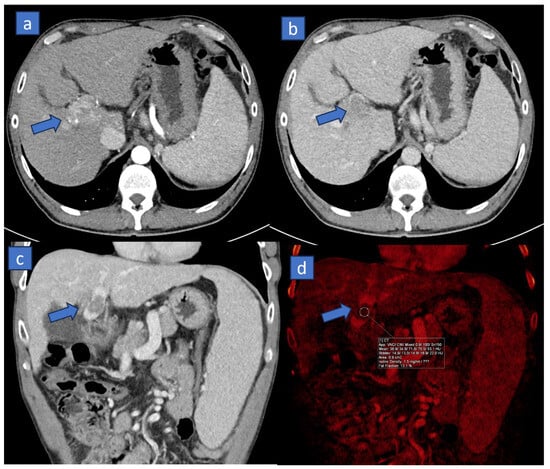

2. Virtual Non-Contrast (VNC)

Applications